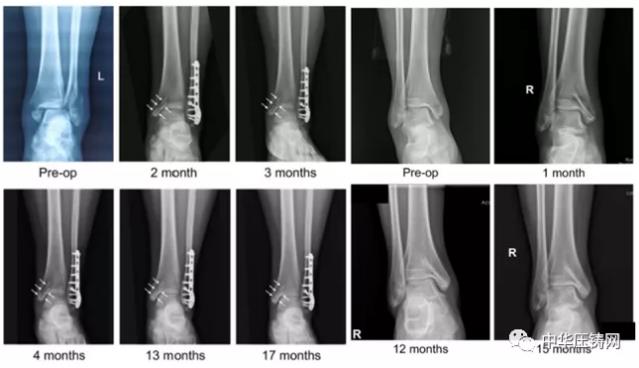

近日,國際骨科臨床轉化期刊《Journal of Orthopaedic Translation》在線發表了由上海交大戴尅戎院士、郝永強教授團隊和丁文江院士、袁廣銀教授團隊合作發表的可降解鎂合金骨釘1-2年的臨床試驗觀察結果,所有患者術后內踝骨折愈合,功能恢復。研究證實了可降解鎂合金螺釘治療內踝骨折的臨床療效及其生物安全性,為全降解鎂合金植入物等高端醫療器械進一步的臨床推廣應用奠定了堅實基礎,相關成果以“Effectiveness and safety of biodegradable Mg-Nd-Zn-Zr alloy screws for the treatment of medial malleolar fractures”為題在線發表于Journal of Orthopaedic Translation,27 (2021) 96–100。這是國內首個可降解醫用鎂合金臨床試驗的公開報道,也是國際首款含有功能涂層的可降解鎂合金骨釘的臨床試驗結果的公開報道,具有里程碑意義。